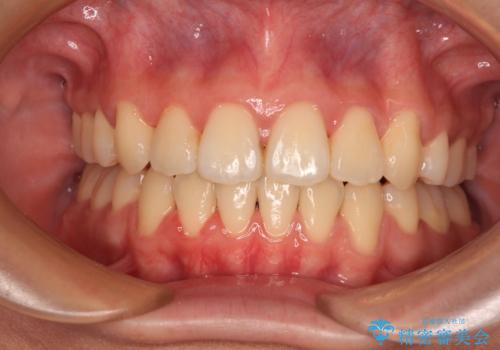

【非抜歯】ガタつきと歯軸を正して長持ちする歯へ

【モニター】前歯のデコボコをインビザラインで改善